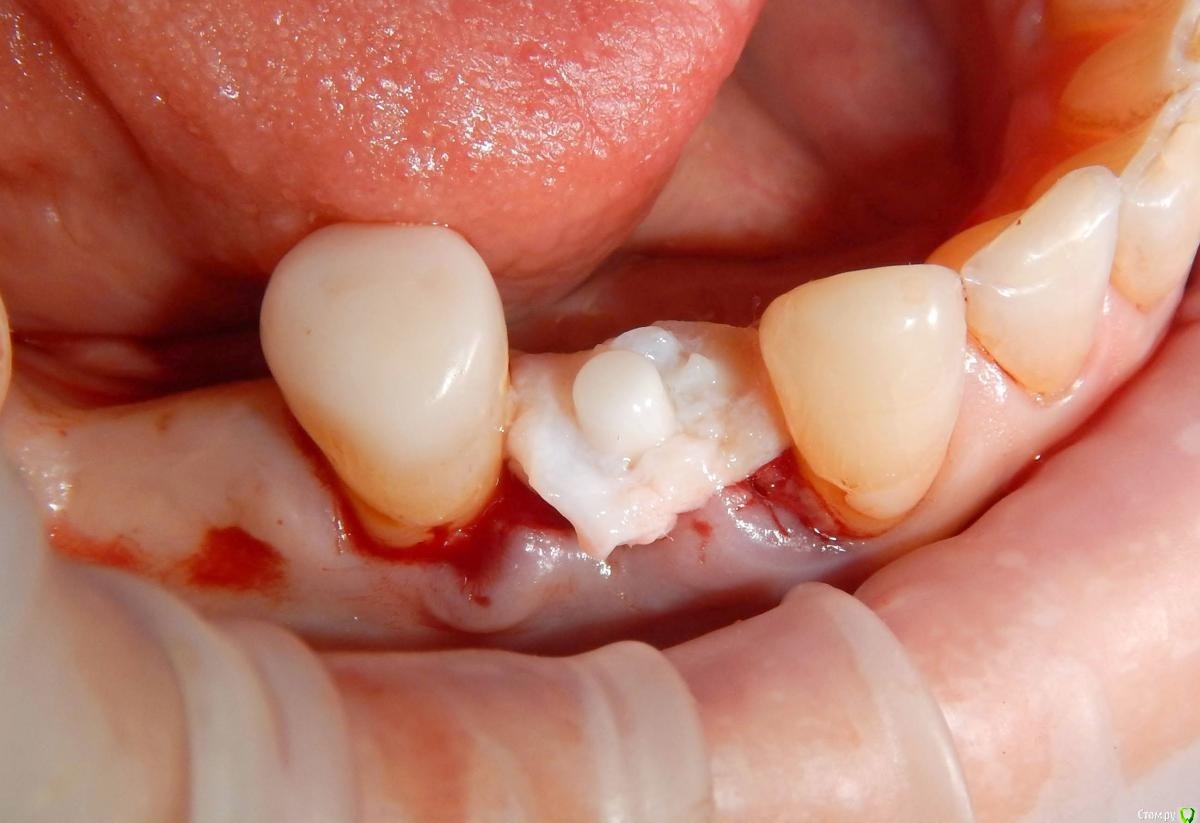

Astronaft Опубликовано 25 января, 2021 Автор Поделиться Опубликовано 25 января, 2021 Спасибо.День операции, 12 недель, день цементировки. 3 1 Ссылка на комментарий

Astronaft Опубликовано 25 января, 2021 Автор Поделиться Опубликовано 25 января, 2021 Уступ доводили вручную? Чем?Имплантат не трогал. На фото черная застёжка (snap on) для оттиска закрытой ложкой - это фабричная деталь. Если доведётся когда-либо доводить уступ - красный алмазный бор. Мелкая алмазная пыль даёт меньшее количество микротрещин. Ссылка на комментарий

Astronaft Опубликовано 24 января, 2021 Поделиться Опубликовано 24 января, 2021 (изменено) Одиночный цирнокиевый имплантат и расщепление без графта. Пациентка:тонкая хрупкая женщина 55 лет, сконцентрированная на своем здоровье, в некоторой мере мнительная.всегда тяжелые заживления после удалений (по опросам)есть результаты Клиффорд теста (такая книжка под 200 страниц с in vitro аллерго-пробами на все известные материалы) Поставленная цель:только цирконий Мне было интересно найти вариант найболее приемленый пациентке и мне. С минимом хирургического риска и риском сожаления пациентки про выбор костного материала. Во-первых, я не использую аллографты - философски, чужие протеины, неприятный запах - просто основываясь на своем мнении.Во-вторых, мнительные пациенты склонны "пойти и почитать" до или потом и как следствие внушить себе вещи которых может и не было. Но по скольку мысль материальна... Все обсудил заранее.План: ридж сплит (расщепление), имплантат без графта, свободный СТ графт; если случается вестибулярная рецессия - пилим зирконий во рту. Ридж сплит сделан пьезотомом - крестальный и вертикальные пропилы на глубины около 8-10мм.Пилотное сверло.Развдвинул кость остеотомами от 1.6мм до 3.5мм в диаметре.Очень мягкая кость - напомнила мегкую максиллу плотности ногтевой пластинки вестибулярно.Имплант встал легко, но торк 40нсм. СТ графт из области 18. Деэпителизирую скальпелем уже потом. Тут интересно отметить, что я перестал боятся ошметков эпителия.Пончо сверху имплантата (а-ля шашлык Карлоса).Швы. PTFE всегда хорош. 12 недель.Красивая десна.Периотест -5.8 - отличный результат.Оттиск. Циркониевая коронка симметричная другой стороне. Изменено 24 января, 2021 пользователем Astronaft 19 Ссылка на комментарий